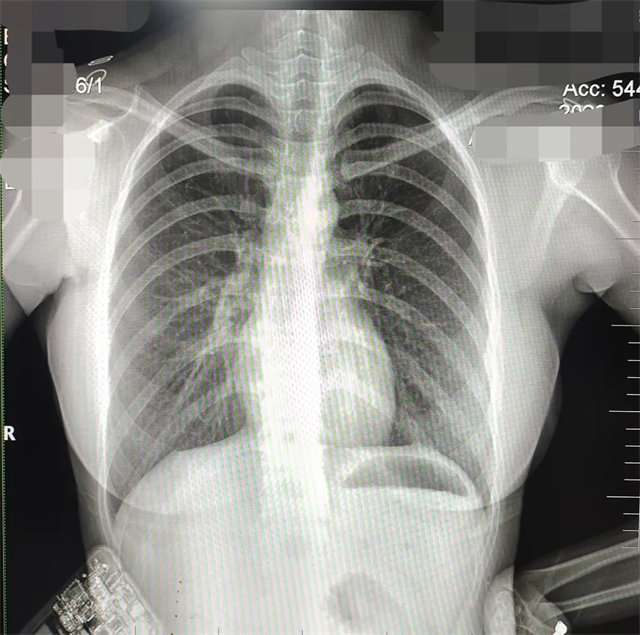

拍攝的不合格胸片的缺陷和解決方法

缺陷:雙側(cè)胸鎖關(guān)節(jié)不對稱,且有手機(jī)顯影。

解決:去除手機(jī)后,使患者左側(cè)緊貼成像件曝光。